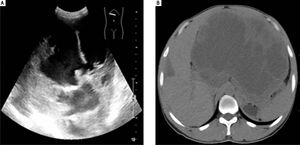

Case ReportThis is a 44 years old male presenting with upper abdominal distension for three months and upper abdominal pain for one week. Physical examination revealed the liver to be extending to 10 cm beyond the rib contour. No liver tenderness was present. Physical examination revealed no jaundice or spider angioma (spider nevus). There was no edema in his body. Superficial lymph nodes were not palpable. Ultrasound examination showed an abnormal liver with a mass in the left lobe with a mixed echo signal and no increased blood flow (Figure 1A). A subsequent computerized tomography examination (Figure 1B) revealed a 21.0 x 16.0 cm mass with an irregular border in the left lobe of the liver. His complete blood counts, total bilirubin, and protein levels were all within normal ranges. Liver enzymes alanine transaminase (ALT) and aspartate aminotransferase (AST) were within normal ranges but gamma-glutamyl transferase (GGT) was elevated (155 U/L, normal range 7-50 U/L). His HbsAg test was negative. Serum AFP and CEA levels were within normal ranges. CA19.9 was elevated to 108.6 U/mL (normal 0-30 U/mL).

Ultrasound examination (A) revealed a mixed echo mass within the left lobe of the liver and the tumor was too large to be measured by this method. Computerized tomography examination (B) revealed a large mass approximately 21.0 cm x 16.0 cm with a mixed density and an irregular border in the left hepatic lobe.